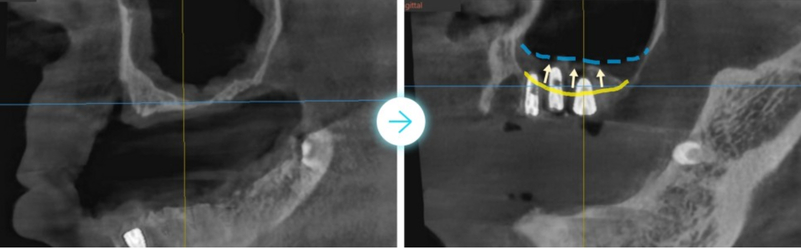

(Ảnh bên dưới) Chúng ta hãy xem kỹ hơn bức ảnh toàn cảnh 3D.

Bạn có thể thấy đường viền nướu vốn đáng ra phải là

đường chấm màu xanh lam nay đã chìm xuống đường

viền màu vàng đậm nằm ở đầu chân răng.

Khi nướu đã tụt đến mức này thì việc răng rụng cũng không có gì lạ,

răng tự nhiên bên cạnh đã ăn sâu vào chân răng nên sẽ rụng sớm thôi.

(Hình bên dưới) Nếu quan sát tình trạng viêm xung quanh trụ implant,

bạn có thể thấy xương nướu ở vùng răng cấy ghép phía dưới đặc biệt bị lõm xuống so với các vùng khác.

(Vạch liền màu vàng là đường xương nướu)

Ngoài ra, xác nhận xương nướu răng hàm trên đã tụt xuống đáng kể, chỉ bằng một nửa so với trụ implant.

Cả hàm trên và dưới đều là những biểu hiện điển hình của viêm quanh implant.